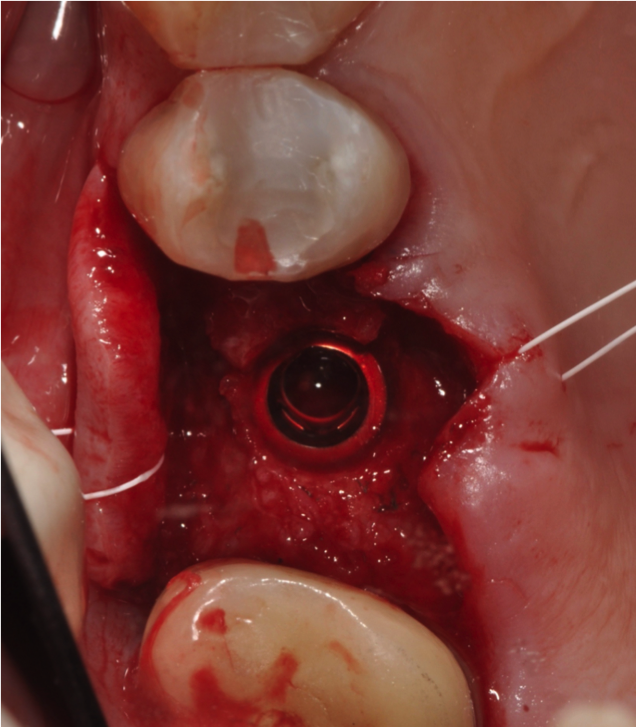

For the surgery, a crestal incision was made, and a flap was reflected to the subperiosteal area to expose the bone. Because of the tight, firm quality of the gingiva, a suture was placed both lingually and buccally to pull the tissue out and ensure that it would not get caught underneath the surgical guide and compromise proper seating. Following the guided surgical procedure, the recommended drilling series was followed to create the osteotomy and insert the implant (Figure 17 and Figure 18), and a postoperative radiograph was taken (Figure 19). A cover screw was attached to the implant, and the flap was sutured over it. The patient was allowed to heal with the implant submerged for 4 months.

Fig 17. Suture to pull tissue out to help ensure proper seating.

Figure 17